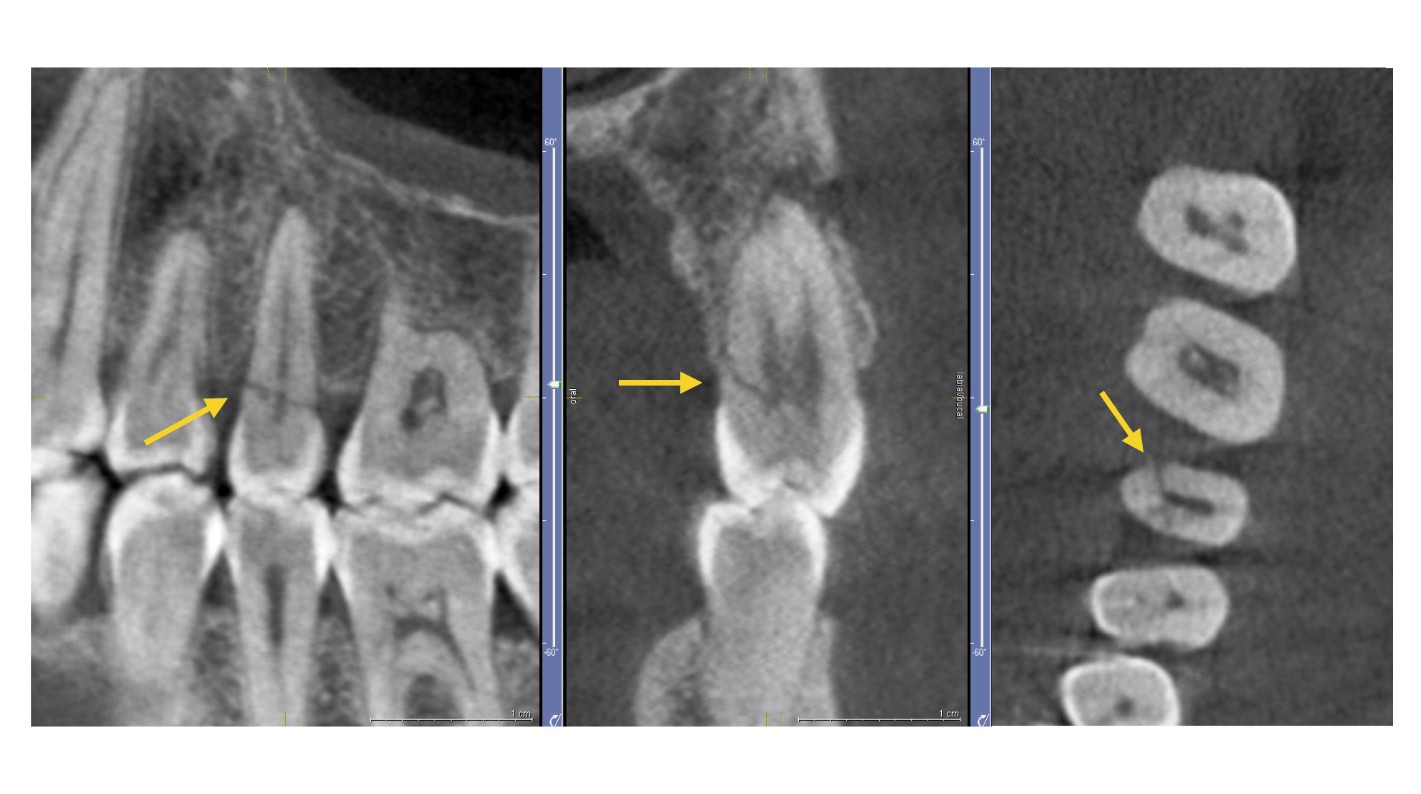

Si tu campo de trabajo es la endodoncia, un escáner CBCT puede aportar la visión axial, coronal y sagital que no puedes obtener con la radiología convencional, aunque esta sin duda es más práctica y adecuada para los procedimientos más habituales en endodoncia. El CBCT tiene gran ventaja en eliminar o reducir la superposición de las estructuras, por ejemplo, para:

Visualizar la anatomía de los conductos radiculares: si utilizas un escáner CBCT con un limitado FOV podrías reconocer con mayor precisión los canales radiculares y aportar mediciones más exactas de las angulaciones de las raíces.

Identificar una patología periapical: con un equipo CBCT se obtendría mayor sensibilidad en el diagnóstico de lesiones periapicales experimentales, sin embargo, no debemos olvidar los artefactos del material restaurador que podrían dificultar el diagnóstico.

Identificación de fracturas en dientes: el escáner CBCT supera a la radiología convencional en el diagnóstico de fracturas dentarias ya que salvo que el haz de rayos esté orientado de modo que atraviese el plano de la fractura, en una radiografía intraoral no es posible separar los fragmentos en la imagen. Nuevamente, este diagnóstico en CBCT se podría ver perjudicado por los artefactos.

Análisis del proceso de reabsorción radicular interna y externa: con tu equipo CBCT podrás no solamente detectar la ubicación exacta, sino que también determinar la extensión de la reabsorción y la comunicación con el espacio del ligamento periodontal.